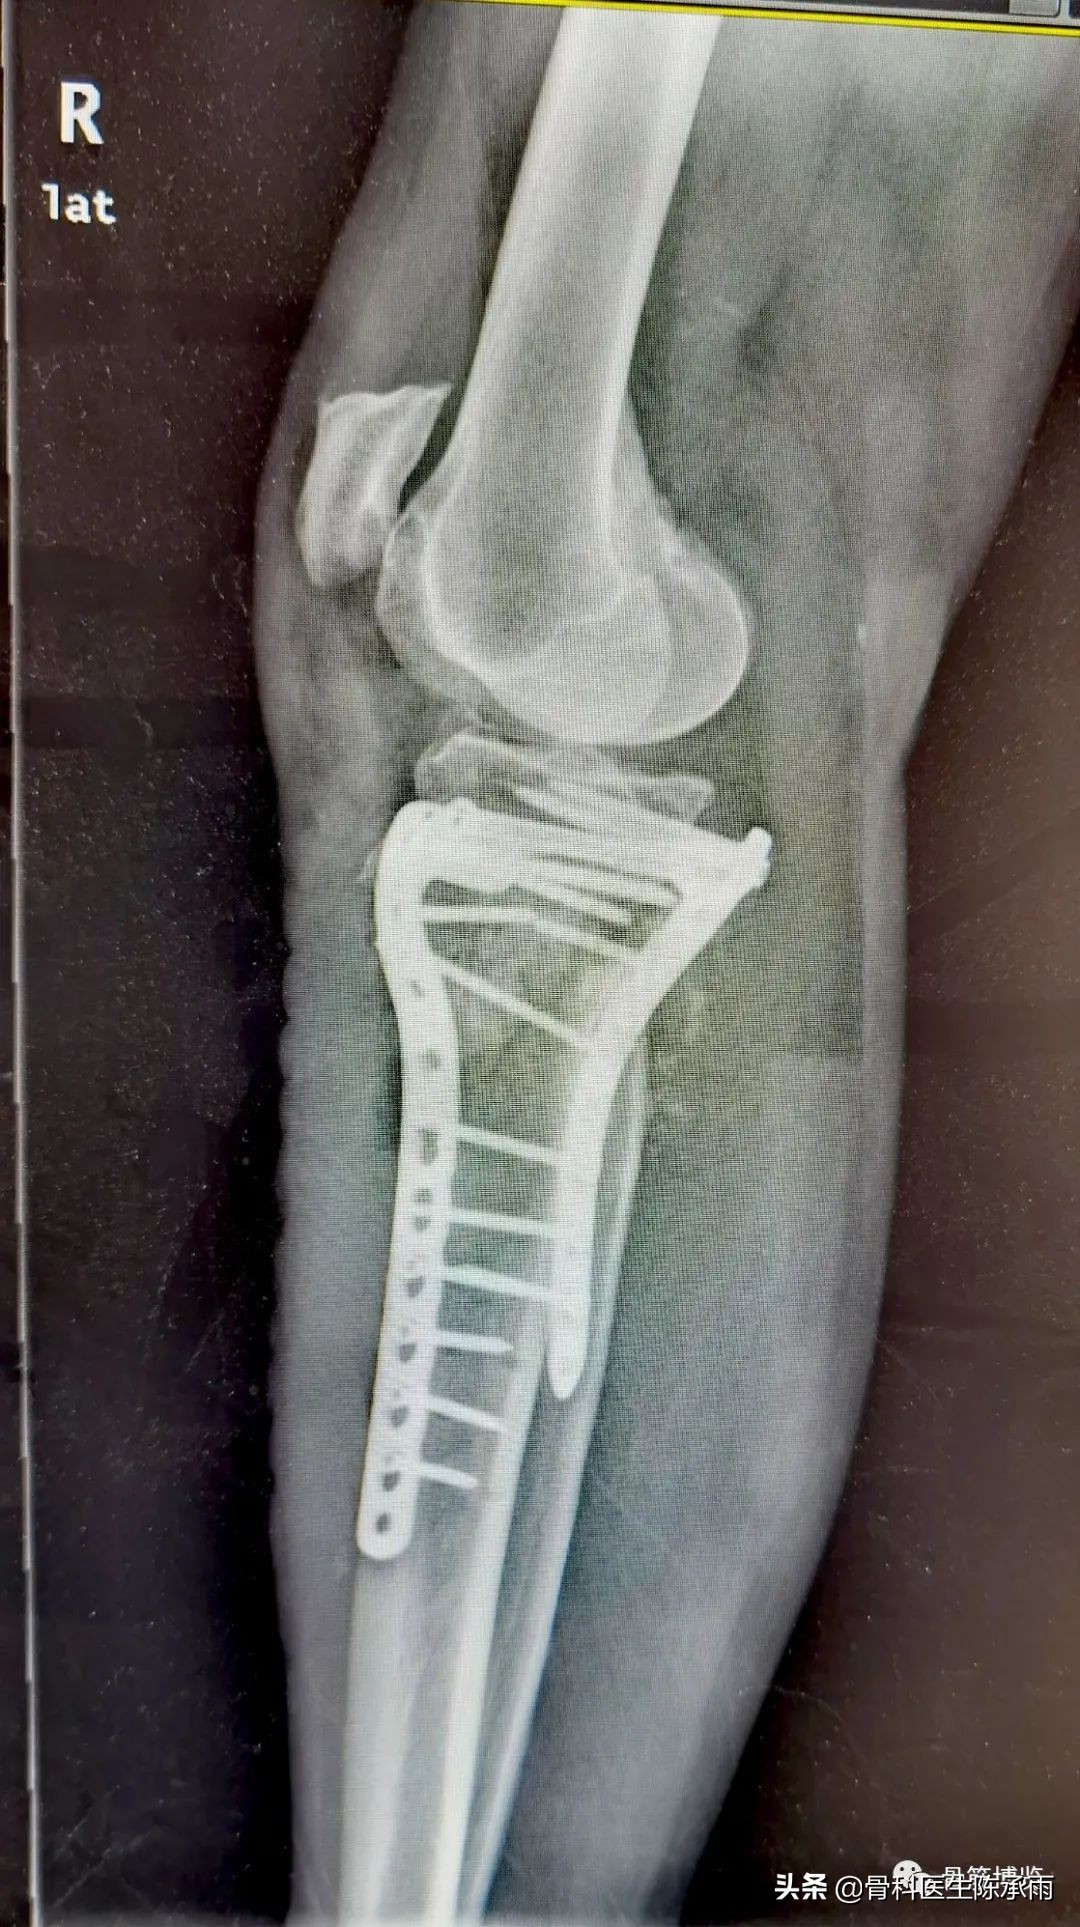

下例胫平台骨折皮肤条件差,内侧板取两端小切口置入内板固定。胫骨结节处撕脱骨折以1枚拉力螺钉固定。